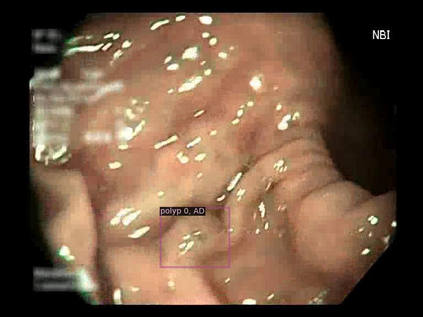

Early detection, accurate segmentation, classification and tracking of polyps during colonoscopy are critical for preventing colorectal cancer. Many existing deep-learning-based methods for analyzing colonoscopic videos either require task-specific fine-tuning, lack tracking capabilities, or rely on domain-specific pre-training. In this paper, we introduce \textit{PolypSegTrack}, a novel foundation model that jointly addresses polyp detection, segmentation, classification and unsupervised tracking in colonoscopic videos. Our approach leverages a novel conditional mask loss, enabling flexible training across datasets with either pixel-level segmentation masks or bounding box annotations, allowing us to bypass task-specific fine-tuning. Our unsupervised tracking module reliably associates polyp instances across frames using object queries, without relying on any heuristics. We leverage a robust vision foundation model backbone that is pre-trained unsupervisedly on natural images, thereby removing the need for domain-specific pre-training. Extensive experiments on multiple polyp benchmarks demonstrate that our method significantly outperforms existing state-of-the-art approaches in detection, segmentation, classification, and tracking.